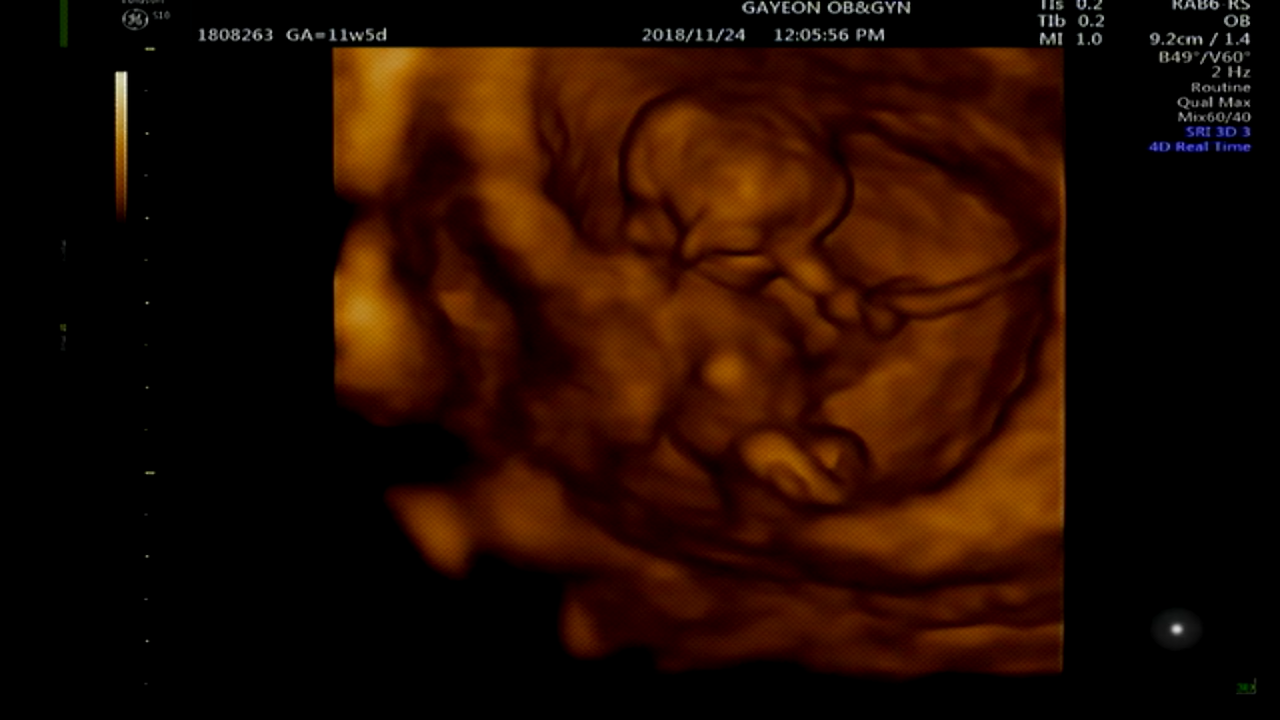

[11W5D] 정밀초음파와 1차 기형아검사.

12W에는 1차 기형아검사를 할 때 쯔음이라 주말에 맞춰 11W5D에 톨이와 함께 가연관악산부인과를 갔다.

KakaoTalk_20181127_115123266.png

꼬톨이는 너무도 건강하게 잘있었다 :)

아직 새끼손가락 크기밖에 되지않아 형태가 자세히 보이지는 않지만 꼬물거리는 모습, 팔과 다리 코까지 볼 수 있었다.

목둘레도 다행히 정상이고, 1차 기형아 검사인 듀얼코드검사(피검사)도 잘 마쳤다.

(목둘레가 정상수치를 넘어서면 다운증후군일 확률이 있다고 한다)